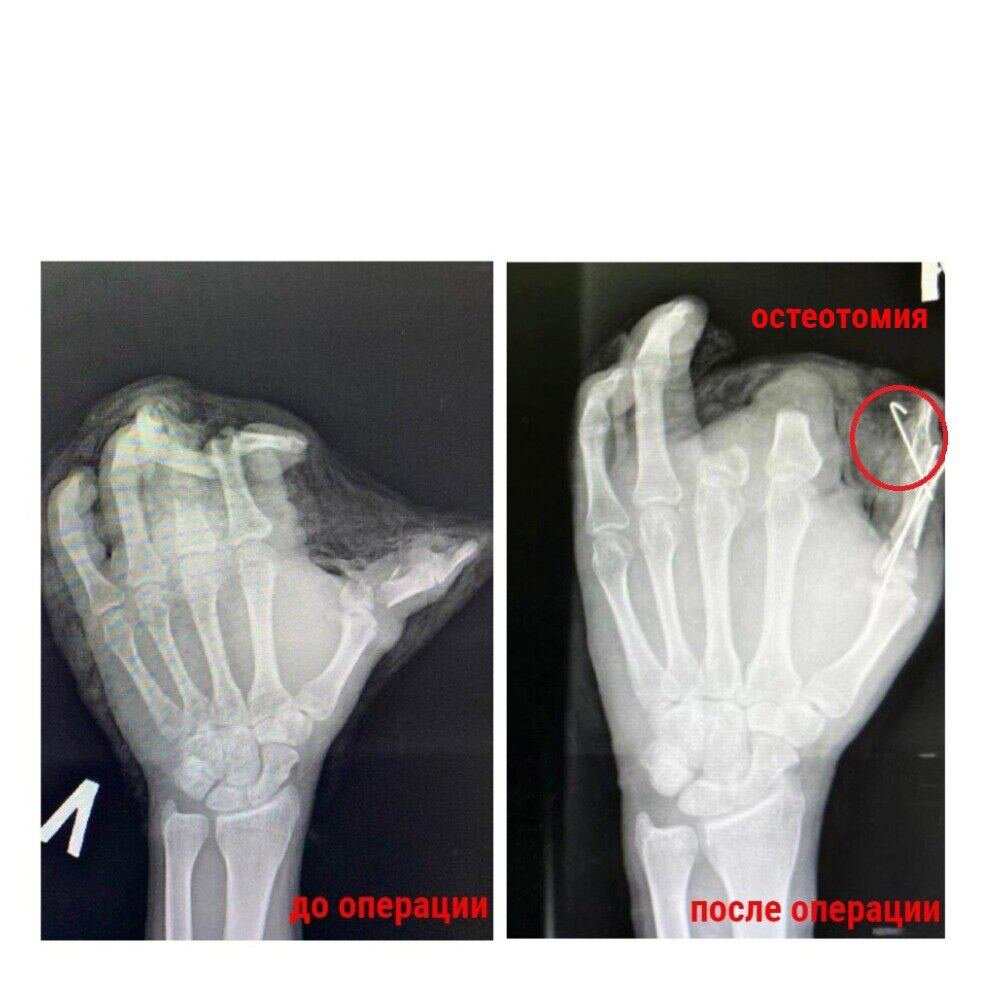

Врачи Красногорской городской больницы прооперировали кисть 38-летнему мужчине, в руке у которого взорвалась петарда. Мужчина поступил в больницу с раздробленной левой кистью, травму он получил во время праздников. Указательный и средний пальцы находились в таком состоянии, что их нельзя было восстановить с помощью остеосинтеза и реплантации. Врачи убрали костные фрагменты и сухожилия, но оставили кожные лоскуты, которые прикрыли ампутированные пальцы, также врачи сформировали эстетически пригодную конечность. Для одного пальца врачи провели остеотомию: собрали кость и провели остеосинтез спицами. Для прикрытия кожного дефекта взяли здоровую кожу с нижней треть предплечья. Лоскут и трансплантат прижились. Мужчина чувствует себя хорошо. Функция кисти восстановилась, инфекционных осложнений удалось избежать.

Врачи Красногорской городской больницы прооперировали кисть 38-летнему мужчине, в руке у которого взорвалась петарда.

Мужчина поступил в больницу с раздробленной левой кистью, травму он получил во время праздников. Указательный и средний пальцы находились в таком состоянии, что их нельзя было восстановить с помощью остеосинтеза и реплантации.

Врачи убрали костные фрагменты и сухожилия, но оставили кожные лоскуты, которые прикрыли ампутированные пальцы, также врачи сформировали эстетически пригодную конечность.

Для одного пальца врачи провели остеотомию: собрали кость и провели остеосинтез спицами. Для прикрытия кожного дефекта взяли здоровую кожу с нижней треть предплечья.

Лоскут и трансплантат прижились. Мужчина чувствует себя хорошо. Функция кисти восстановилась, инфекционных осложнений удалось избежать.